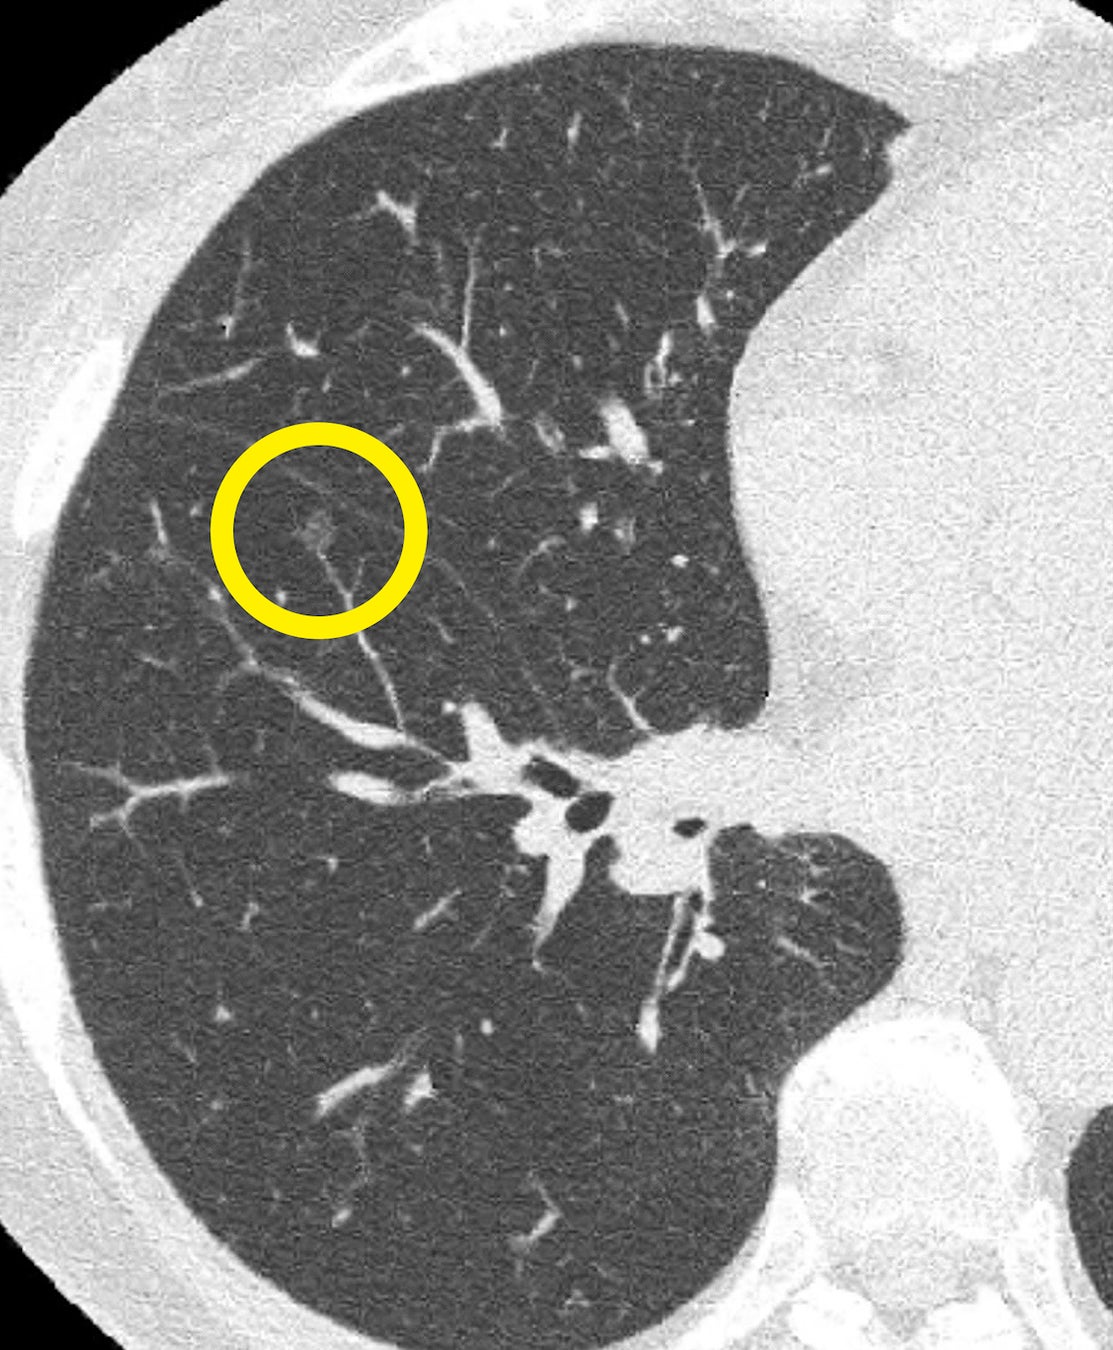

尿がん検査「マイシグナル」を提供するCraif株式会社(所在地:東京都文京区、CEO:小野瀨 隆一、以下Craif)は、第42回 呼吸器外科学会学術大会にて、北海道大学病院 加藤達哉教授らと共同で実施した肺がんに関する前向き観察研究(*1)「北海道でのマイシグナルを用いた肺癌スクリーニングの有効性の検証」の成果を発表いたしました。今回の取り組みでは、マイシグナルの検査結果から肺がんのリスクが高いと判定された方が精密検査を受け、肺がんの疑いのある腫瘍が発見されました。その結果、手術によりステージ0の肺がん(AIS: Adenocarcinoma in situ)を取り除くことができ、完治に至りました。

本研究は、Craifが肺がんリスクが高い方を対象に「マイシグナル・スキャン」を100セット無償提供し、「マイシグナル・スキャン」でリスクが高いと評価された方をフォローアップし、肺がんの診断率を評価したものです。さらに、年単位での追跡調査を通じて、肺がんの罹患率や予後への影響、関連する因子の特定を目指しています。今回の追跡調査の結果、マイシグナル検査で肺がんのリスクが高いと判定された方が精密検査を受け、肺がんの疑いのある腫瘍が発見されました。その結果、手術によりステージ0(AIS)の肺がんを取り除くことができ、完治に至りました。